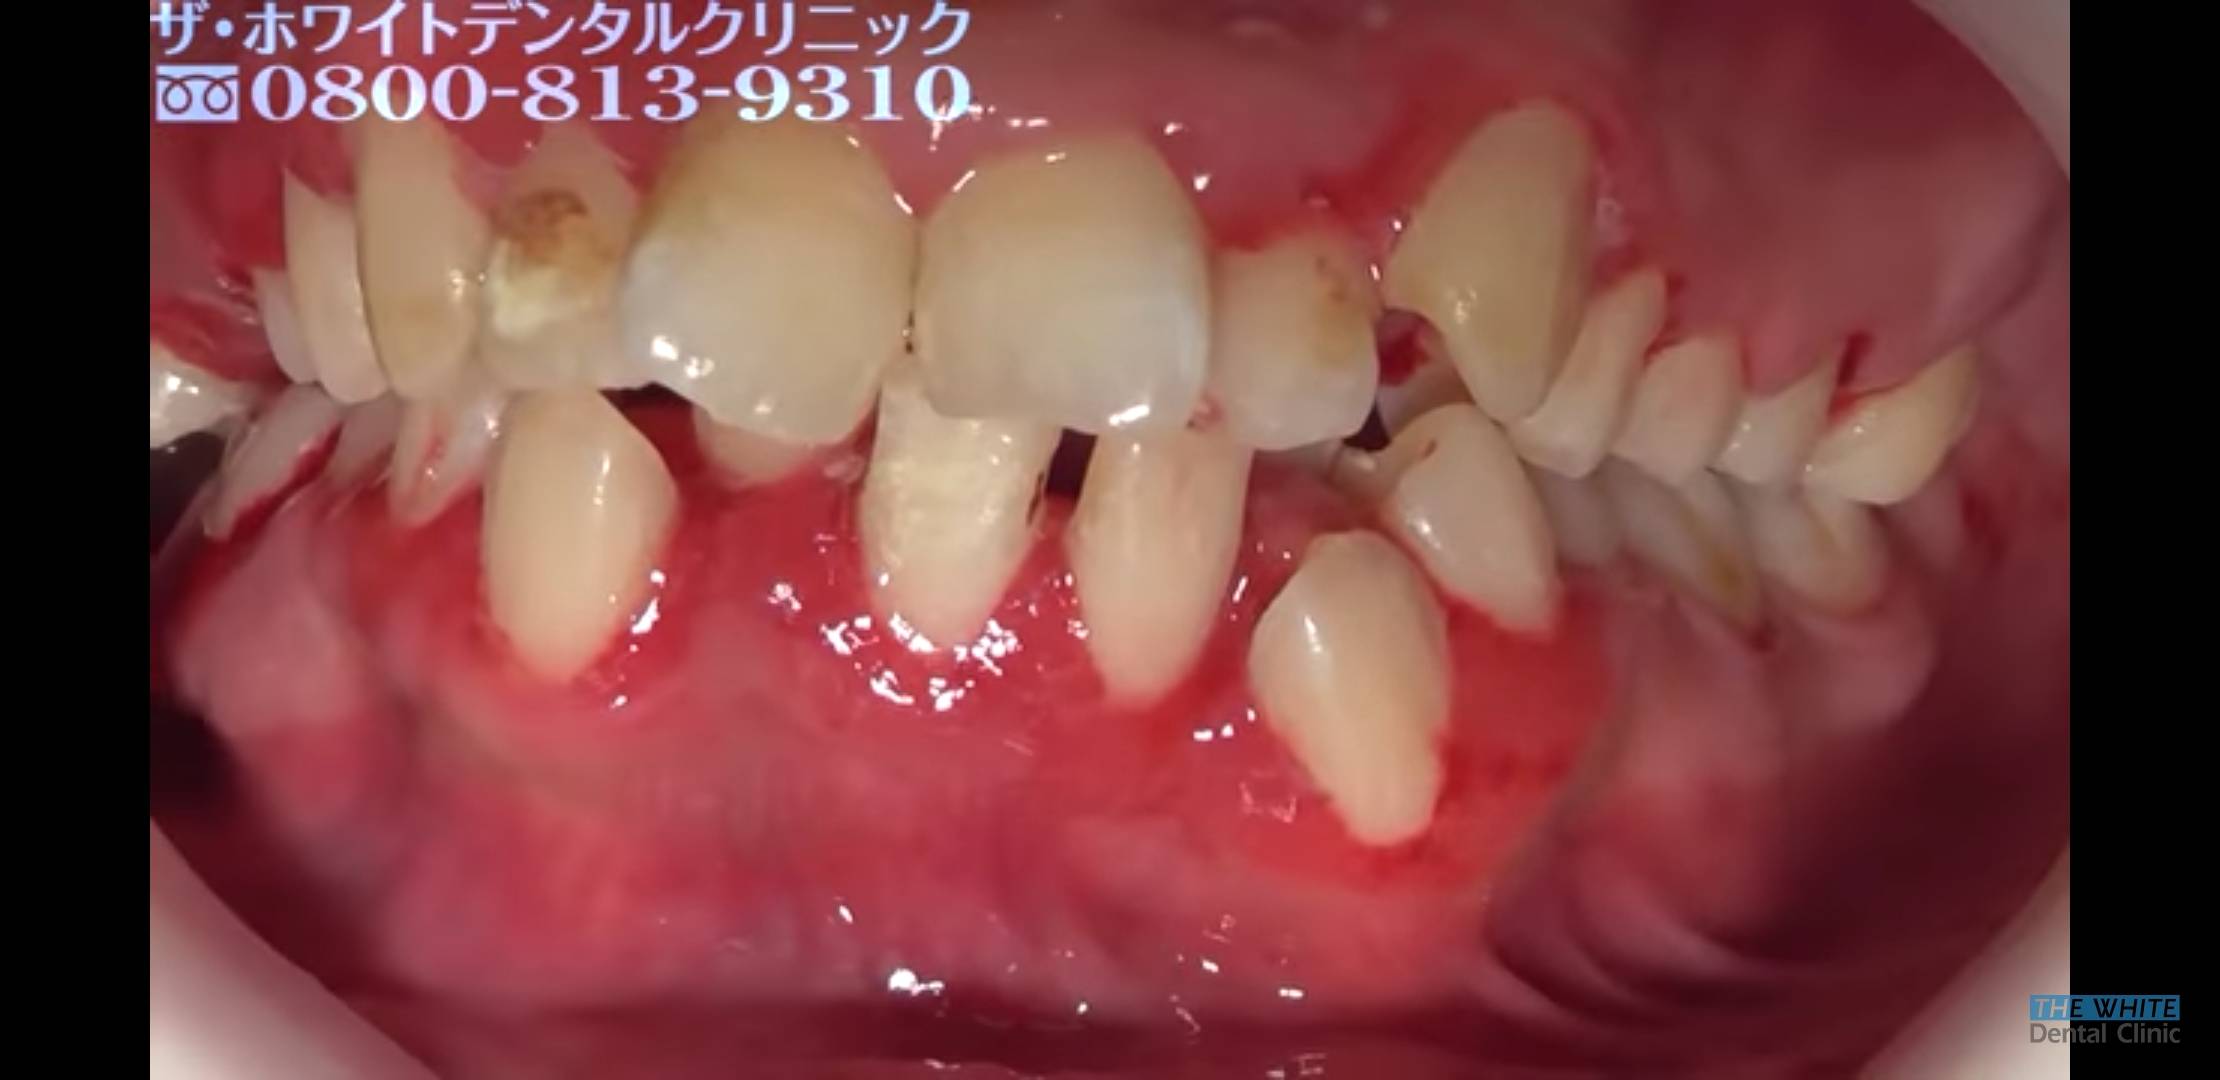

[일반] (드러움) 왜녀(25세) 치석제거

이건 뭐 칫솔없냐?

치열도 자유롭네

이런건 단순히 치솔질을 안한게 아니고 병인가?

치열이 고르지 못해서 칫솔질 제대로 안될듯